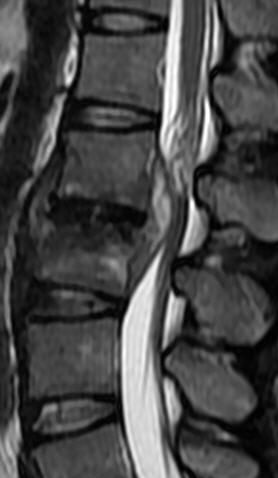

MRI

可提供腰椎管的矢状面、冠状面和轴位横断面上的影像。椎管狭窄以T2加权像显示较好,脑脊液为高信号,产生所谓“脊髓造影”的效果,而骨质增生,骨赘、间盘均为低信号,能清晰地显示椎管狭窄,以及对脊髓的压迫情况。但对肥大的黄韧带、骨质增生等的判断则不如较高清晰度CT扫描。

腰椎正常MRI解剖。

腰椎管狭窄MRI表现。